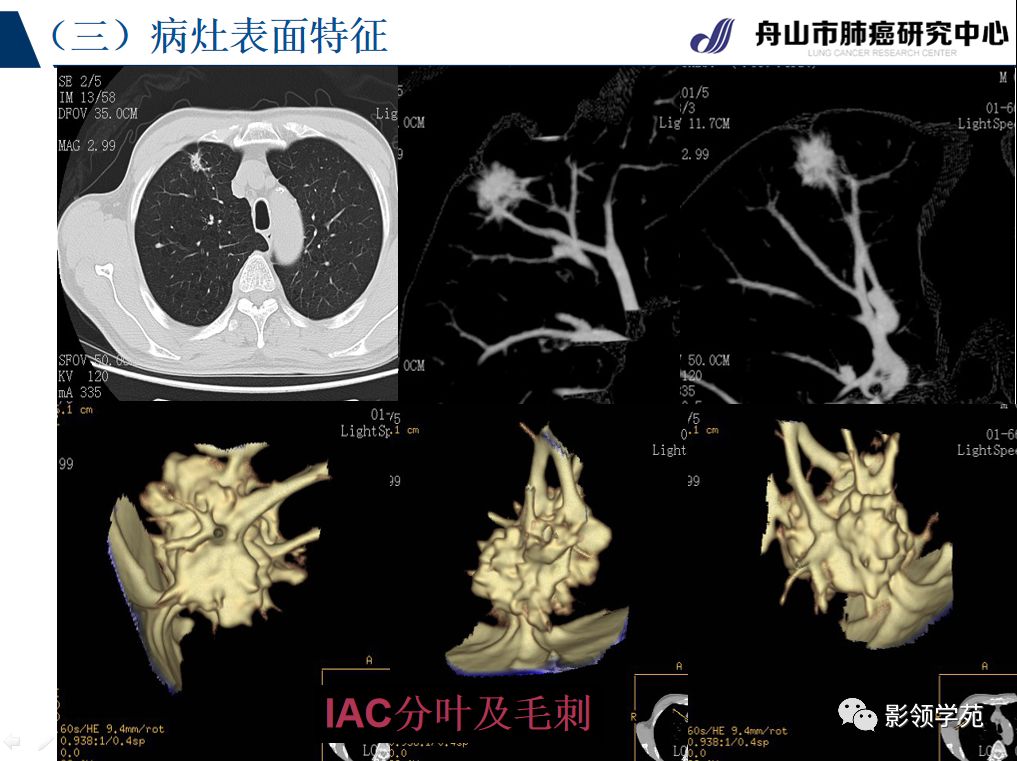

血管征 空气支气管征 ct征象小结: 所有征象认定均在ct三维重建基础

病灶内血管与支气管情况 动态观察 所有征象判断基于肺结节三维重建